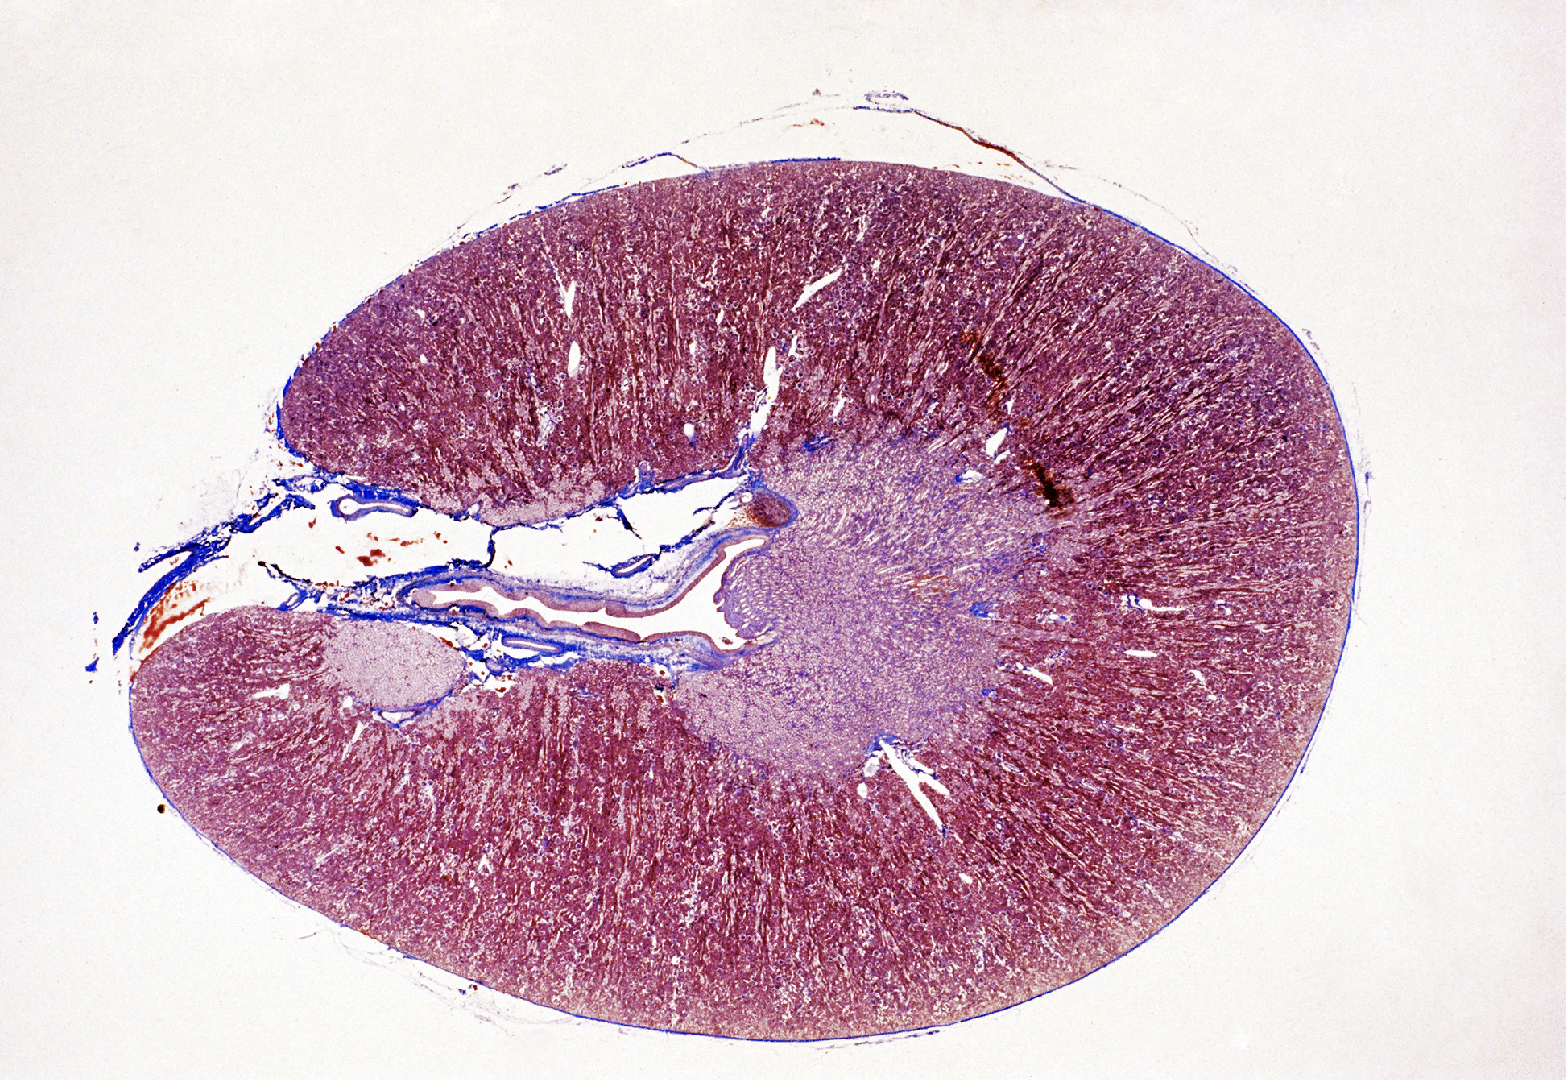

List layers of Kidney (Low magnification view)

7

New cards

High magnification of renal cortex- list different parts